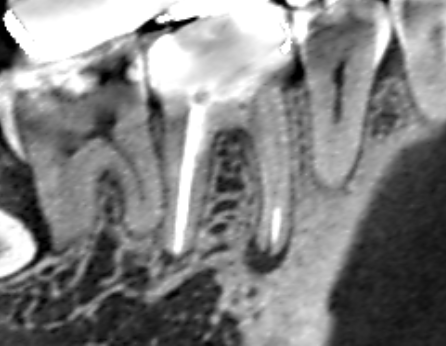

下顎第一大臼歯の近心根の先に膿がみられたケースです。近心根には2本の根管があり、両方とも根管治療…